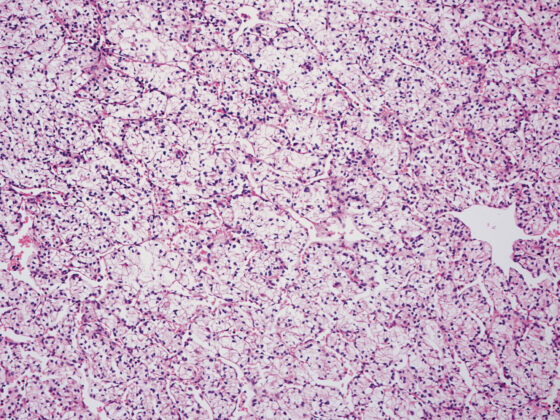

Anämien sind eine häufige Erscheinung in der ärztlichen Routineversorgung, deren Ursachen vielfältig sein können. Eine Anämie bezeichnet eine Verminderung des Hämoglobin- und Hämatokritwertes. Der Cut-off-Wert von Hämoglobin beträgt bei weiblichen Erwachsenen <12 g/dl (<7,44 mmol/l) und bei männlichen Erwachsenen <13 g/dl (<8,06 mmol/l). In diesem Artikel sollen insbesondere Autoimmunerkrankungen als Ursache für Anämien näher betrachtet werden.